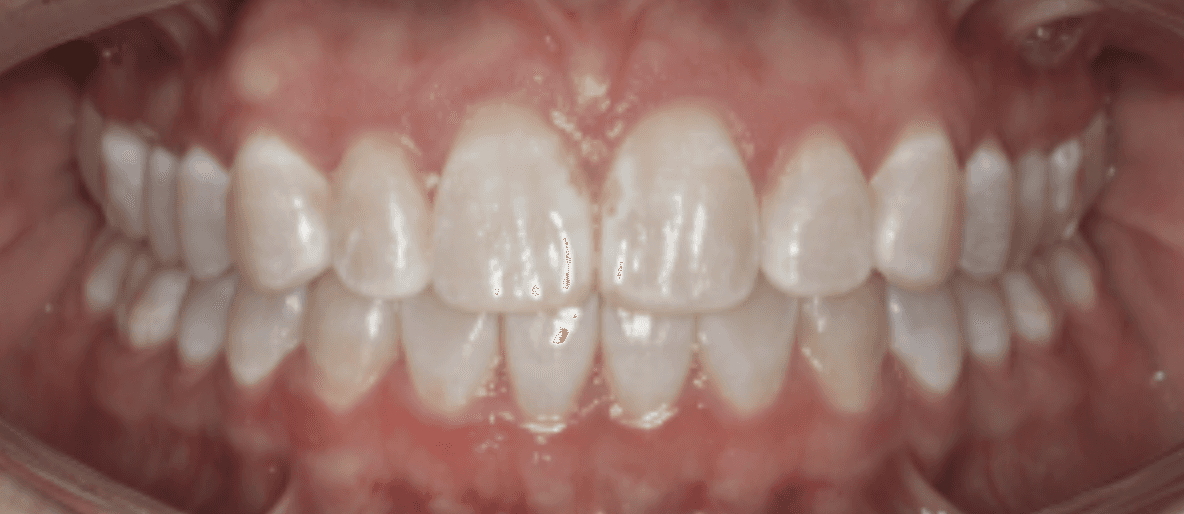

Diagnosis: Deep bite, lower anterior crowding, rotated upper lateral, arch misalignment, wear on teeth from grinding

Adjuncts: Attachments, IPR

Initial treatment

INTRAORAL